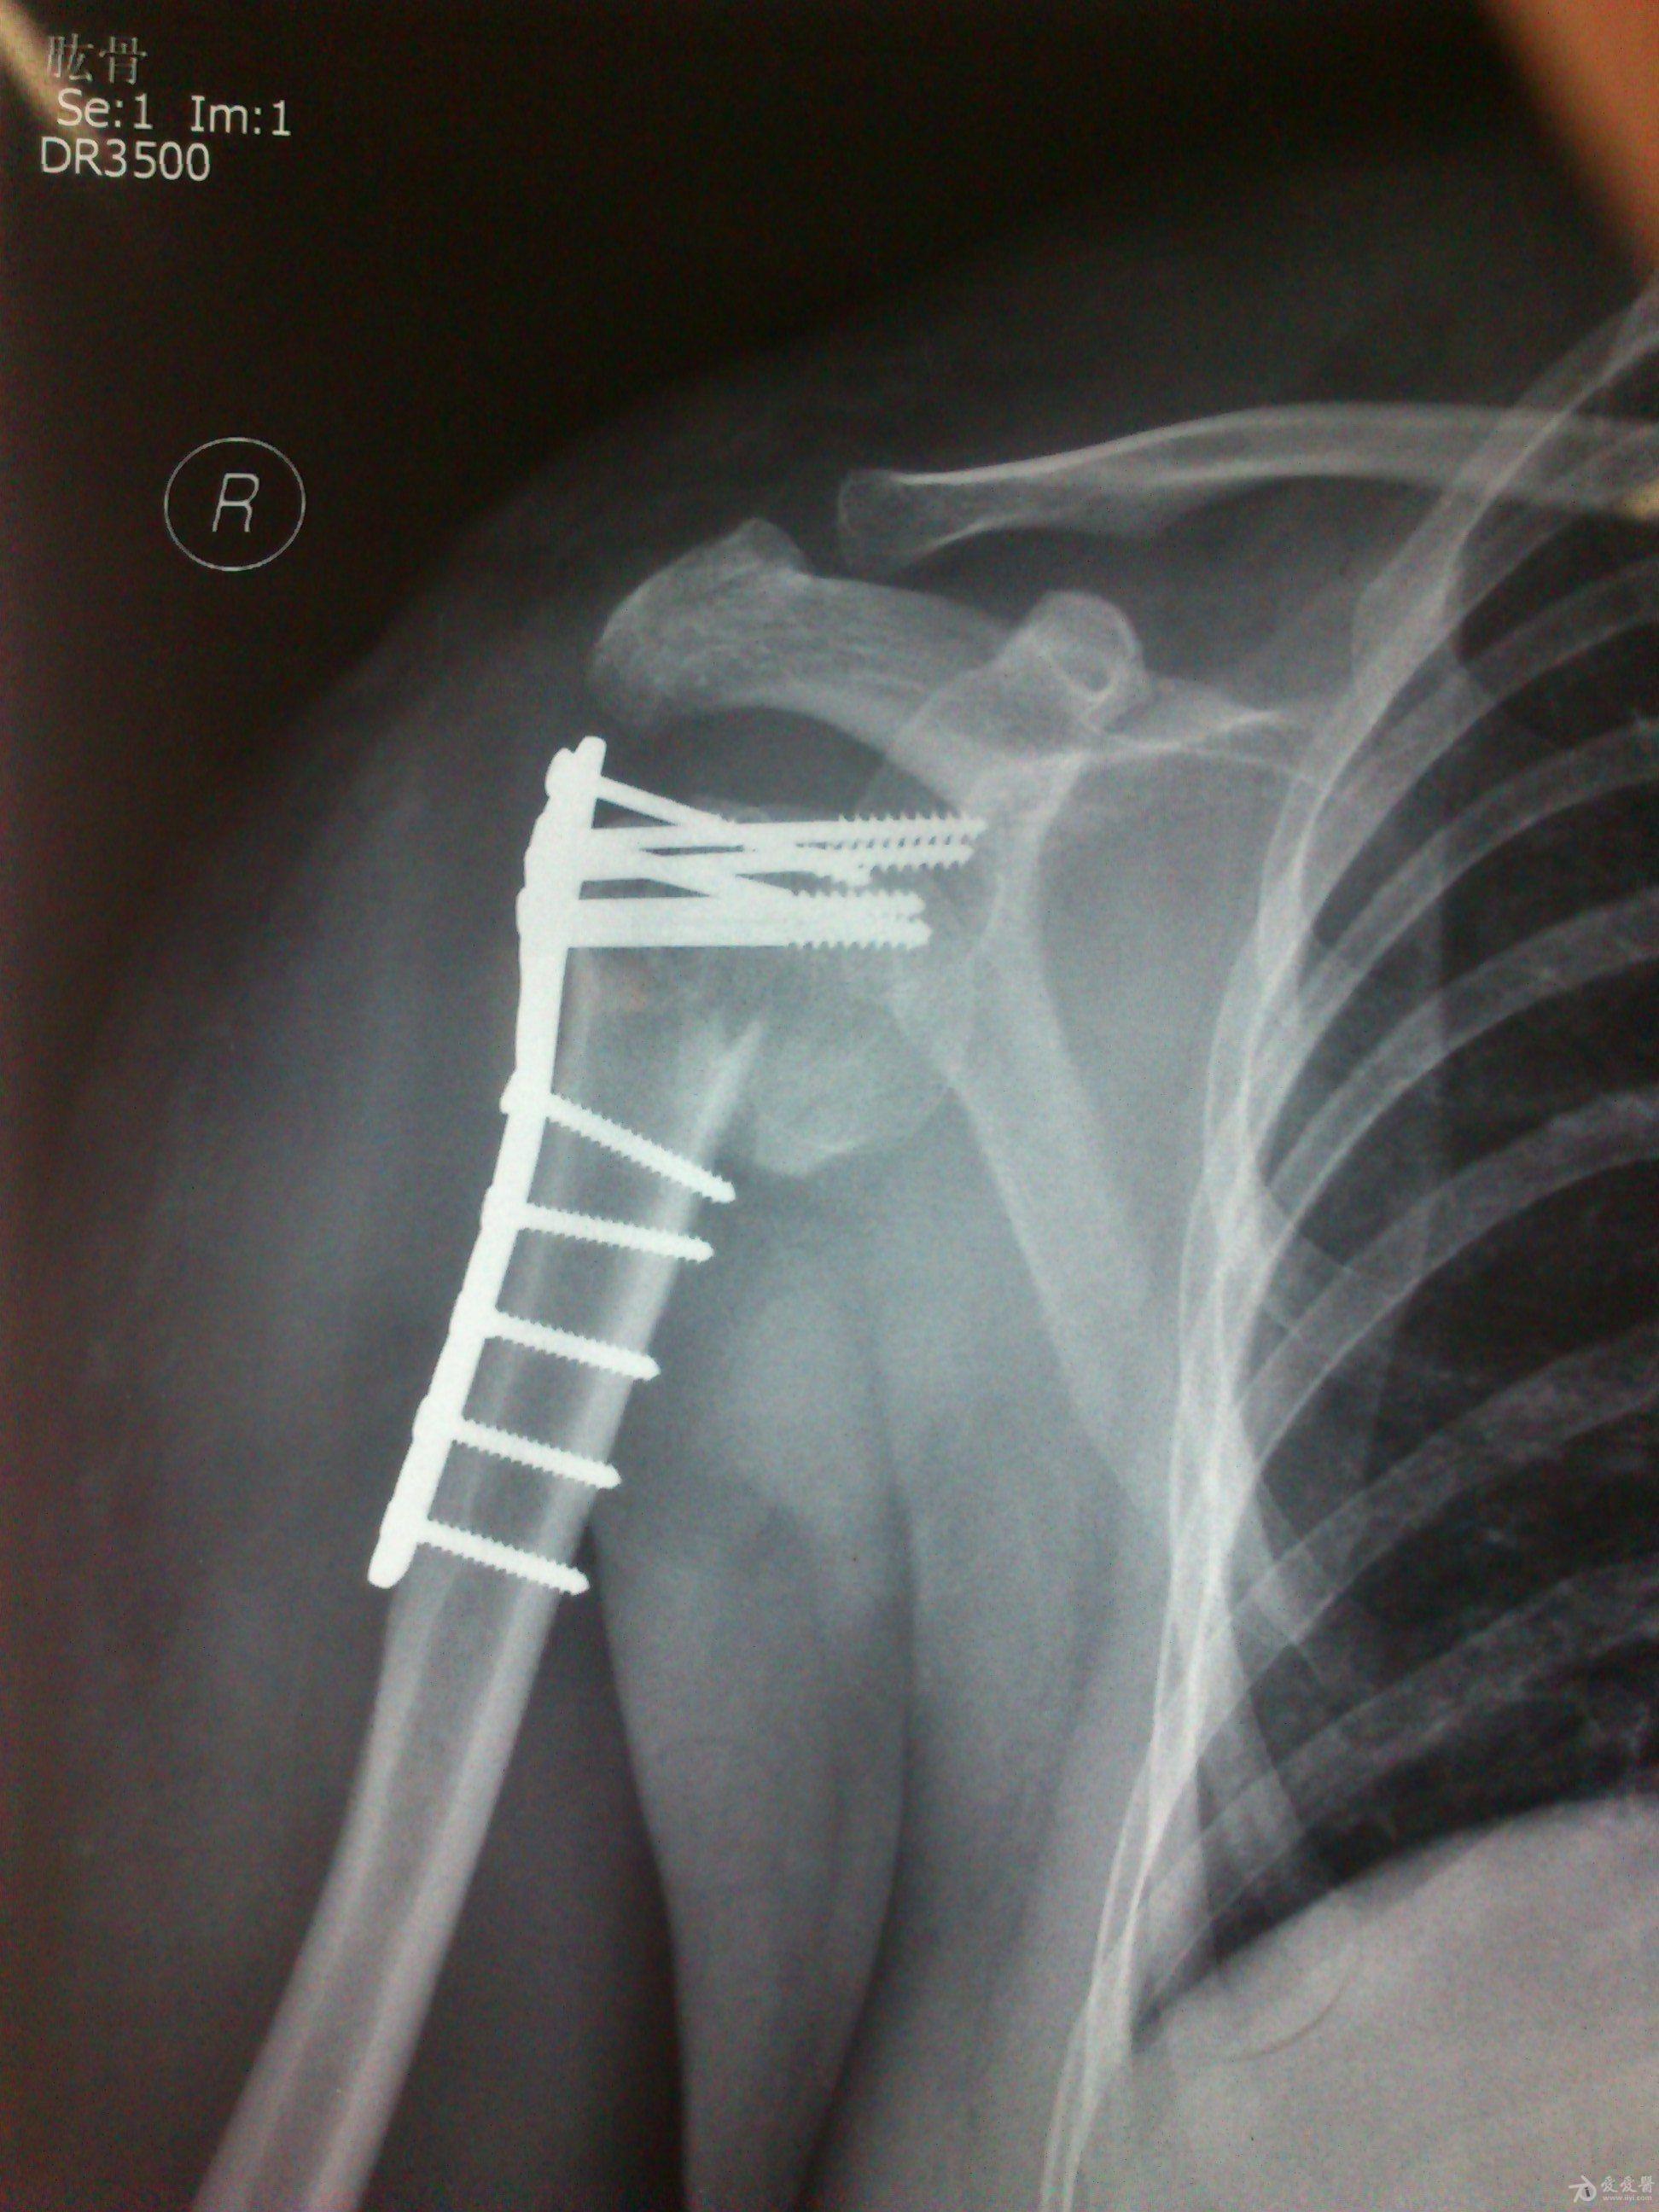

病史特点及病情摘要:1、患者女性,51岁。2、患者自诉入院前1年余因右肱骨外科颈骨折在外院行切开复位内固定术,术后右肩关节疼痛、活动受限,一直未予处理,今为明确诊治入院。患者精神、食欲、睡眠尚可。3、既往史、个人史、家族史无特殊。4、入院查体:生命征平稳,心肺腹检查未见异常,NS(-)。专科情况:右上臂近端内侧见一约15cm手术切口疤痕,愈合佳,右肩关节能外展20度,前屈、后伸及旋前、旋后功能障碍,余关节活动好。舌质红,苔薄白,脉实。5、辅助检查:右肩关节正侧位片:右肱骨外科颈骨折内固定术后再骨折伴右肩关节脱位。

诊断:右肱骨外科颈骨折内固定术后再骨折伴右肩关节脱位

院外术后

同意楼主观点,患者第一次手术复位欠佳,但可勉强接受。但钉子穿出,是手术后肩关节疼痛的主要原因,现在看骨折已愈合,头无明显头坏死迹象,只需取出内固定,麻醉下活动肩关节,使肩关节活动度改善,术后加强功能锻炼,应该恢复不错。